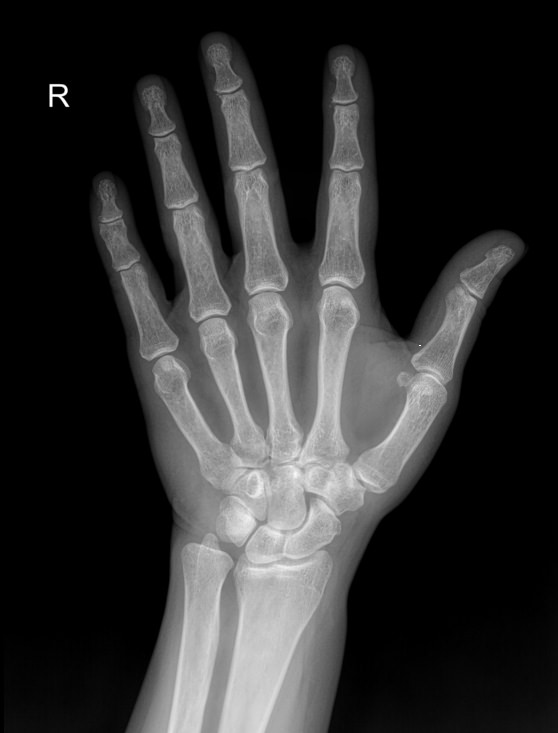

Ладонь и пальцы ― один из самых сложных участков в организме человека. Здесь сосредоточено огромное количество мелких суставов, каждый их которых может воспалиться или быть поврежденным в результате профессиональной деятельности и спорта. Изменения, связанные с возрастом или хроническим заболеванием, также влияют на состояние и функции кистей рук.

Болезни кистей серьезно ухудшают качество жизни, поэтому такие патологии редко игнорируют. Однако их симптомы схожи, что требует тщательной диагностики перед тем, как выбрать метод лечения. Одно из базовых исследований ― рентгенологическое. Это простое, быстрое, информативное и недорогое исследование. Современное цифровое оборудование, которое используют в клинике «Доступная медицина», во время процедуры несет минимальную дозу облучения. Это делает рентген практически безопасным методом обследования.

Что показывает рентген кисти

В протоколе рентгенолог описывает изменения, которые произошли в области исследования:

• Состояние суставных щелей;

• Соответствие друг другу суставных поверхностей;

• Патологические изменения поверхности суставов;

• Состояние костной ткани ― травматические и дегенеративные деформации;

• Возможные новообразования;

• Мягкие ткани.